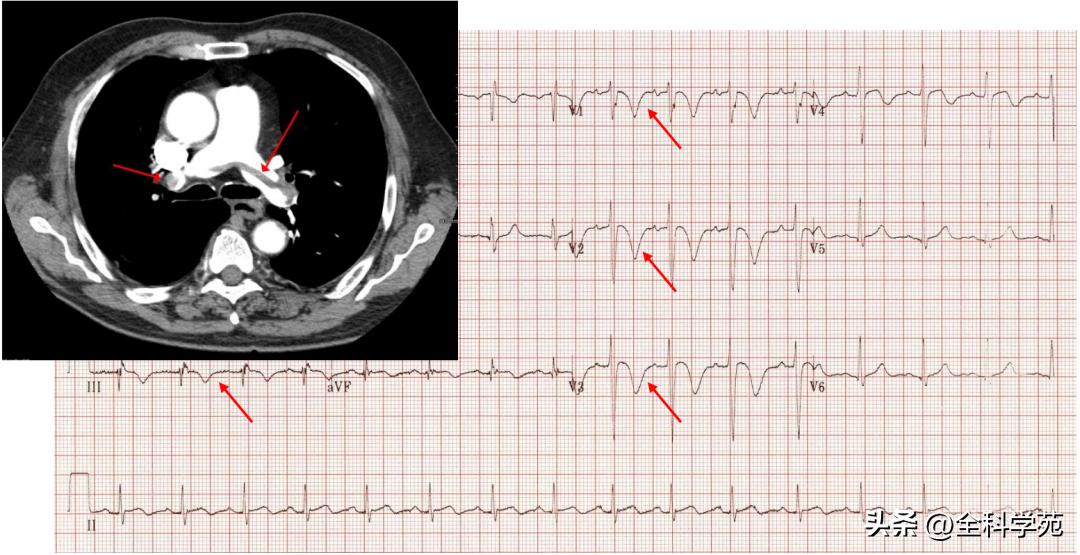

(二)肺栓塞

- 急性肺栓塞引起的T波倒置最常发生在右胸V1~V4导联,常有III导联并存

- T波多呈双支对称性倒置,发生时间多在急性肺栓塞后1~2个小时,随着病情发展呈动态变化

- 其机制可能为:其一,急性肺栓塞时右室压力负荷迅速增加,导致右室扩张及收缩、舒张功能不全,引起牵张力增加,使T波倒置;其二,肺栓塞也可导致右室心外膜下急性心肌缺血,形成T波倒置

- 如图,心率69次/分,可见P波振幅增高(>2.5mv),右胸(V1~V2)导联T波倒置,典型SIQIIITIII征及不完全右束支传导阻滞,患者最终诊断肺栓塞